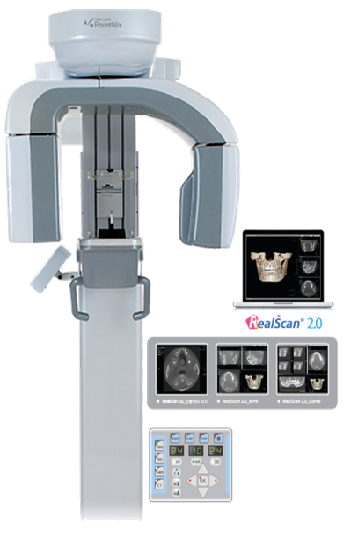

Технические характеристики аппарата:

Входное напряжение 110 ~ 230 VAC 50/60 Hz

Напряжение на трубке 40 ~ 90 kV

Диаметр фокусного пятна – 0,5 мм

Минимальная фильтрация – 2,6 мм (Al)

Анодный ток – 4 - 16 мА

Угол расхождения лучей - 50

Время экспозиции в панорамном режиме – 17 сек.

Время экспозиции в режиме КТ – 19 сек.

Технические характеристики сенсора:

Модификация – Varian (Flat Panel Detector)

Панель детектора – плоская (Amorphous Silicon) – 14 - bit

Размер пикселя 127х127 микрон

Размер вокселя – 0,183

Толщина среза – 0,16 мм. (макс.)

Поле зрения (FOV) – 100х90 мм.

Размер 3D снимка – 387 Мб. (449 frames – 120х85)

Время реконструкции – 10 – 40 секунд

Системные требования к конфигурации ПК:

Pentium-4, 3 GHz и выше

CPU Intel Core i5-2400 и выше

VGA Card - NVIDIA Geforce GTS 450, 1G RAM

RAM (оперативная память) – минимум DDR3 3G

Свободный PCI-слот 2 pcs и PCI-Express 1 pcs

Наличие 9-ти пинового COM-порта (сериал порт)

ОС - Windows 7 32 bit only

Технические характеристики цефалостата (опция):

Тип приемника - flat panel detector (TFT Selenium)

Размер пикселя – 129 микрон

Разрешение изображения – 2.048х1.536 пикселей (3,1 Mpix)

Время экспозиции – 0,8 – 17 сек. (One-Shot Cephalo or Scan)

Активная площадь сенсора – 198х264 мм.